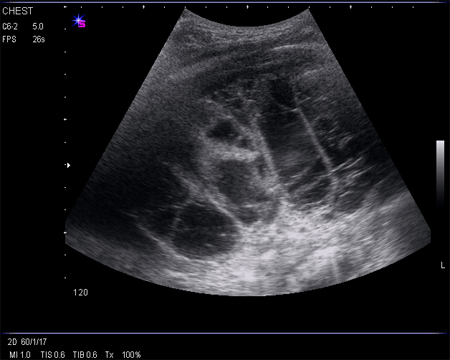

Ultrasound image of heavily septated empyema

From the collection of Najib Rahman, RTU, Oxford